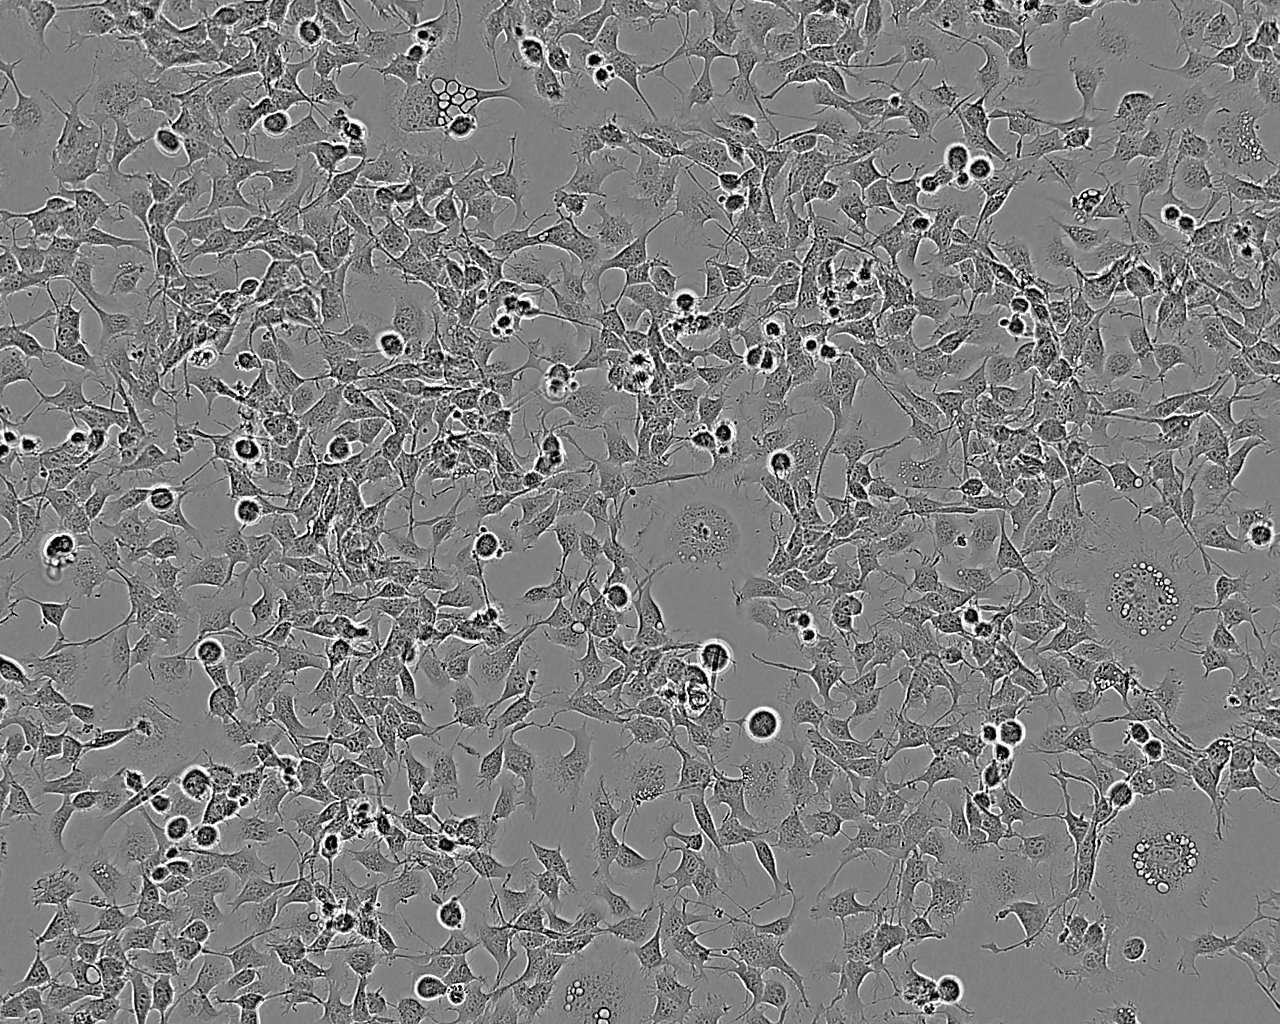

细胞生长:贴壁

细胞背景资料:U-251 MG分离至一位患者的胶质母细胞瘤组织。

细胞形态:上皮细胞样

细胞生长特性:贴壁